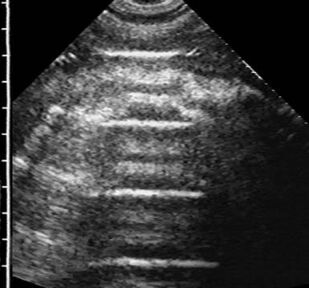

В книге в практическом аспекте изложены вопросы ультразвуковой диагностики опухолей лёгких: показаны возможности и ограничения трансторакальной эхографии при выявлении внутрилёгочных объёмных образований, приведена методика исследования и нормальная эхокартина грудной клетки, подробно освещена ультразвуковая семиотика центрального и периферического рака лёгкого, включая эхопризнаки про# растания опухоли ворганы средостения или грудную стенку. Детально изложены вопросы дифференциальной диагностики онкологической патологии лёгких при синдроме безвоздушной лёгочной ткани и синдроме пристеночного образования. Впервые представлен комплекс симптомов для определения внутри- или внелёгочной локализации пристеночного образования. В отдельной главе рассмотрены субплевральные очаговые образования неопухолевой этиологии: инфаркт лёгкого, очаговый фиброз, жидкостные кисты, артериовенозная аневризма и другие редкие заболевания. Книга иллюстрирована большим количеством эхограмм, отображающих основные диагностические признаки рассматриваемой патологии.